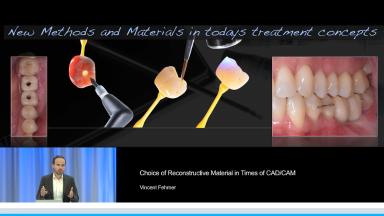

Choice of Reconstructive Material in Times of CAD/CAM

Ceramic materials are increasingly used for the fabrication of dental reconstructions. However, because there are so many options for fabricating ceramic prostheses, the selection of an ‘ideal’ material is becoming more and more complex. This lecture presents concepts for choosing the type of reconstruction, material, and method of fabrication for a highly esthetic outcome. Long-term survival rates, advantages, and limitations for new ceramic methods and materials - in particular high-strength ceramic zirconia - are presented in this lecture. The results of clinical studies comparing digital CAD/CAM and conventional workflows for fabrication of all-ceramic restorations are also presented.

- explain the indications and limitations of the new CAD/CAM technologies

- describe the selection of and indications for CAD/CAM monolithic restorations

- discuss the ideal implementation of the Ti-Base concept